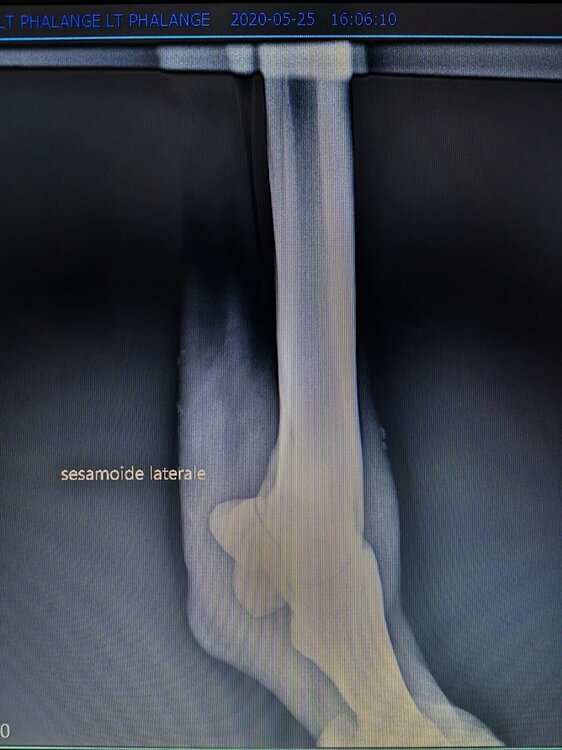

Salve volevo chiedervi qualche informazione in merce tò a un problema che ho avuto con la mia puledra. Qualche settimana fa mentre stavo lavorando alla corda è scivolata urtato l'arto posteriore sinistro. Arrivati in box ho messo dell'acqua a pressione perché si era gonfiato sia il nodello sia il pastorale. Già l'indomani l'arto era sgonfio ritornato normale, quindi ho continuato a lavorarla. Ma dopo qualche giorno di lavoro alla corda leggerissimo, al rientro in box ho notato che sia il nodello che il posturale gonfiavano nuovamente. Allora ho chiamato il veterinario che ha detto che la cavalla aveva una lussazione e mi ha insegnato come cura una fasciatura con della creta per 24h per cinque giorni e un antinfiammatorio. Dopo un paio di giorni la fasciatura ha fatto come delle vesciche e il gonfiore è aumentato dal pastorale alla garra. Abbiamo chiamato un altro veterinario abbiamo fatto vedere anche a lui la cavalla e diceva che poteva essere la frattura del ditino, ma si dovevano fare le lastre per essere sicuri. Ora abbiamo fatto le lastre e il radiologo dice che c'è dell'infiammazione ma non c'è niente di grave. Il veterinario,viste le lastre dice che deve essere operata. Allora abbiamo consultato un'altro veterinario che dice che la cavalla non ha assolutamente niente. Ora io vi allego le radiografie, datemi un vostro parere perché non só più cosa fare. Grazie